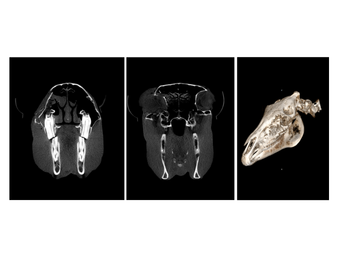

The Asto Equina is a dual-limb, fan-beam CT unit that is capable of imaging equine limbs from the carpus/tarsus down to the foot, as well as the equine head and neck. Scan acquisition is fast and able to be completed in a standing, sedated horse. This fan-beam unit captures excellent bone and soft tissue detail, allowing for diagnosis of a wide variety of pathologies.

In this presentation, Dr. Jack Caldwell of Virginia Equine Imaging (VEI) discusses how Asto CT’s standing fan-beam CT is being used in private equine practice to improve diagnostics, treatment planning, and outcomes for performance horses. Dr. Caldwell walks through real-world clinical cases involving sport horses, jumpers, dressage horses, and eventers—highlighting how standing CT has enhanced the evaluation of complex lameness, distal limb pathology, neck conditions, head trauma, and surgical planning. These cases demonstrate how CT imaging can reveal pathology that may be underestimated or missed with radiographs, ultrasound, or low-field MRI alone.